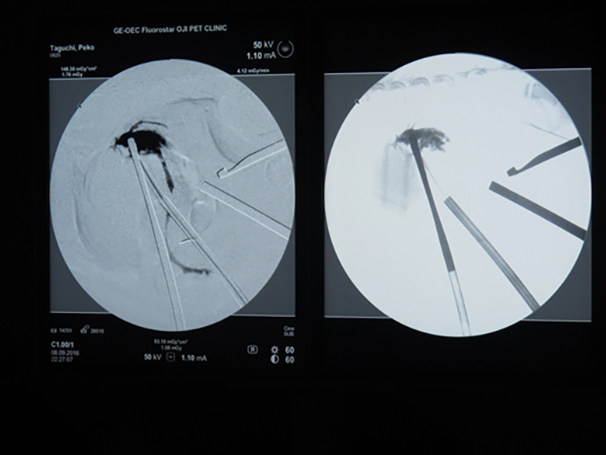

胆嚢の通路がちゃんと開通しているのか調べるために造影検査をしています。 この処置をすることで洗浄の効果と詰まりを確認することができます。

詰まりがないかを透視で確認しています。